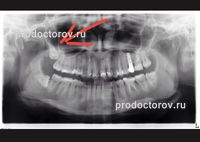

Прикладываю фото.